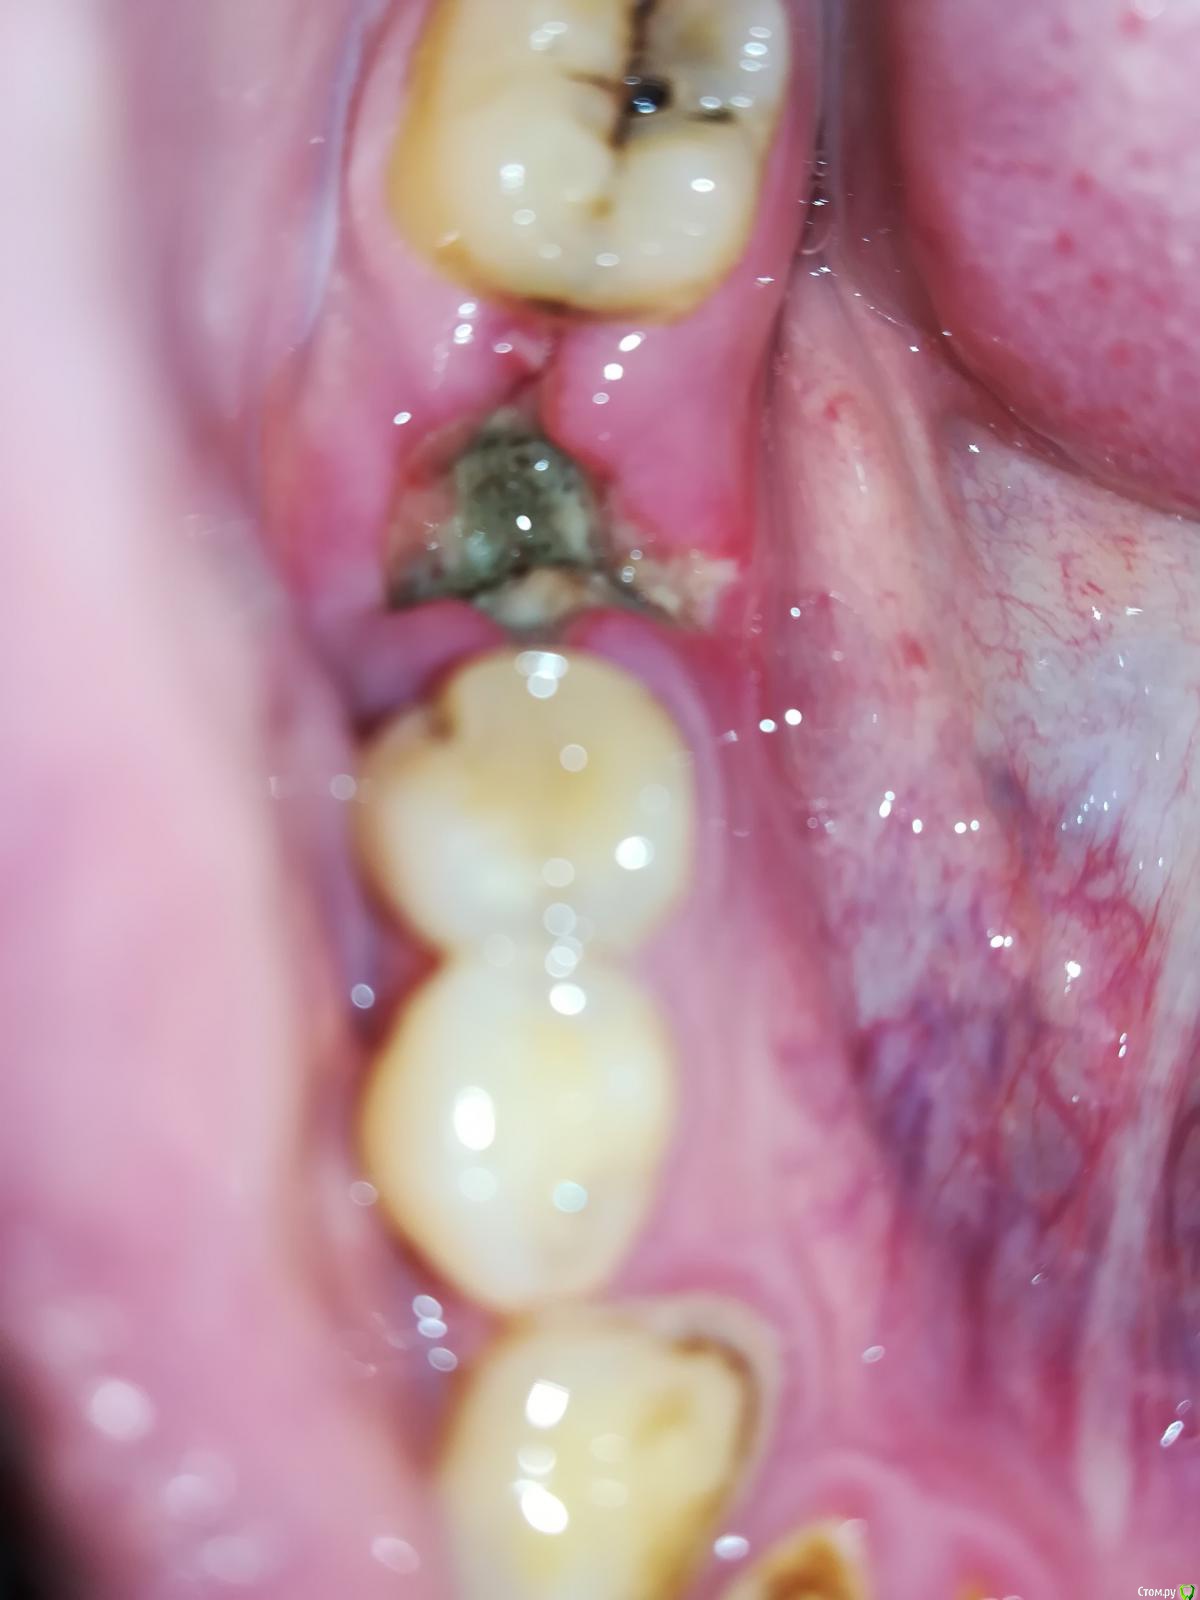

r7zh Опубликовано 1 мая, 2018 Поделиться Опубликовано 1 мая, 2018 (изменено) Здравствуйте! После удаления шестого нижнего зуба прошло 5-6 дней, десна не болят (только первые 2 дня), покраснение тоже отсутствует, температура в норме, по рентген снимку доктор сказал, что удаление прошло хорошо, ничего не осталось. Только беспокоит неприятный запах из лунки.По фото можно определить или нормально проходит заживление? Спасибо, с уважением. Изменено 1 мая, 2018 пользователем r7zh Ссылка на комментарий